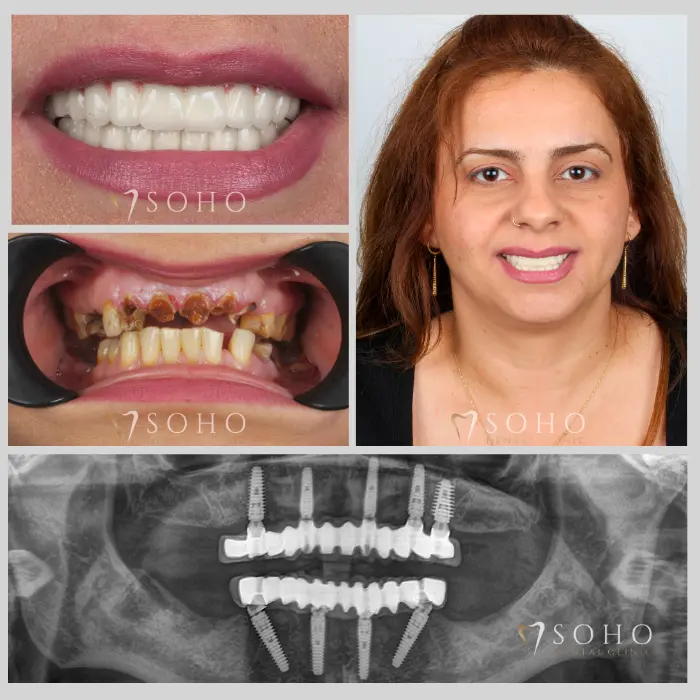

Real Patients. Real Smiles.

Explore the journey of our international patients through authentic visuals, elegant transformations, and moments captured inside Soho Dental Clinic. Let their stories inspire your own.

From First Visit to Final Smile.

Explore real patient stories captured in every transformation. These are more than smiles — they are renewed confidence, achieved with care and precision at Soho Dental Clinic.